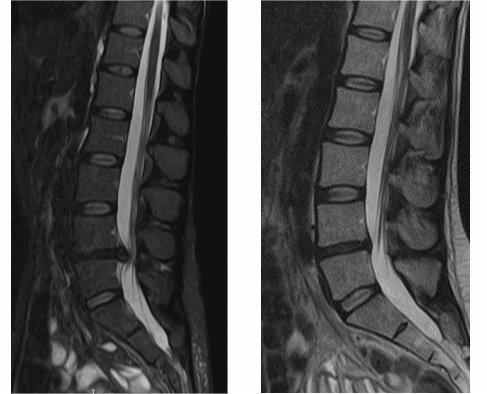

Осмотрели Ирину неврологически и ортопедически, исследовали позвоночник на МРТ и рентгене. Оказалось, что у нее очень большая левосторонняя грыжа размером 12 мм.

На МРТ показано излечение грыжи диска (до- и после лечения).

Контрольный МРТ, через 5 месяцев показал полное отсутствие грыжи диска (см. снимки Ирины ниже):

Обратите внимание на даты проведения МРТ в правом нижнем углу. МРТ исследования проведены на одном аппарате 1.5 теслы в клинике «Меддиагностика» в процессе лечения Ирины. МРТ позвоночника позволяет отследить динамику уменьшения грыжи диска.